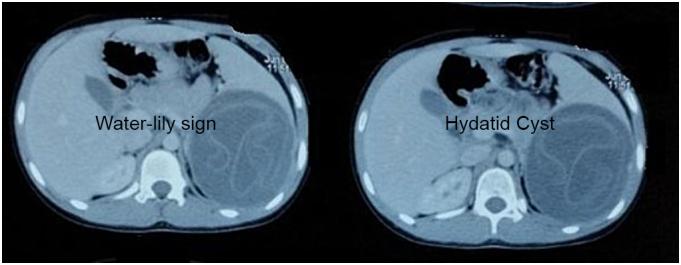

A 14-year-old female presented with left upper quadrant pain. Imaging revealed a large splenic cyst without evidence of liver or lung involvement. A total splenectomy was performed, and a histological examination confirmed the diagnosis of a hydatid cyst. The patient underwent postoperative albendazole therapy and remained asymptomatic during follow-up.

Isolated splenic hydatid cysts are rare in the pediatric population. Imaging techniques such as ultrasound and CT play a crucial role in diagnosis. Surgical resection and Puncture-aspiration-injection-reaspiration remain the choice of treatment, supplemented by anti-parasitic therapy. Postoperative follow-up is essential to monitor for recurrence.

一名14岁女性因左上腹疼痛就诊。影像学检查显示一个大的脾囊肿,无肝脏或肺部受累迹象。行全脾切除术,组织学检查确诊为包虫囊肿。患者术后接受阿苯达唑治疗,随访期间无症状。

孤立性脾包虫囊肿在儿童人群中罕见。超声和CT等影像学技术在诊断中起关键作用。手术切除和穿刺抽吸注射再抽吸仍是治疗选择,并辅以抗寄生虫治疗。术后随访对于监测复发至关重要。